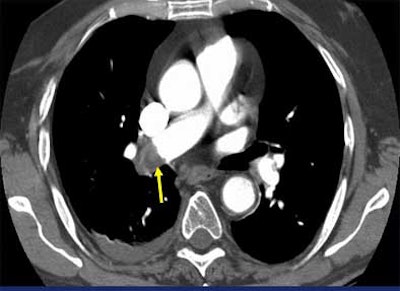

Moreover, a suspected saddle embolus doesn't justify a pulmonary angiogram, though surgeons and internists often seem to think it does, Mayo said. For one thing, a pulmonary angiogram is difficult to do in the presence of a large saddle embolus because it results in a dilated right ventricle. For another, saddle emboli create a significant flow blockage that is easily detectable on CT, he said.

| Saddle embolus. Images courtesy of Dr. John Mayo. |